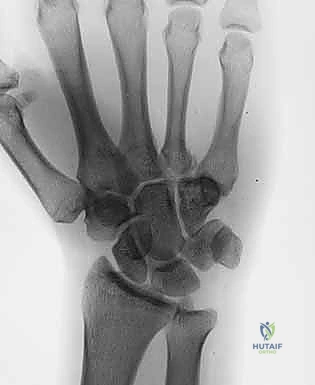

يُعتبر التشخيص الدقيق هو حجر الزاوية في نجاح العلاج. المشكلة الكبرى في كسور وخلع مفصل الكربوميتاكاربال هي أن التراكب التشريحي لعظام الرسغ والمشط في صور الأشعة السينية الأمامية الخلفية (AP View) العادية يجعل من الصعب جداً رؤية الخلع.

- صور الأشعة السينية المتخصصة (X-Rays): لا يكتفي الدكتور بالصور التقليدية، بل يطلب وضعيات تصوير خاصة (مثل الوضعية المائلة Oblique View بـ 30 درجة) التي تظهر قاعدة المشط بوضوح وتكشف الخلع الخفي.

- الأشعة المقطعية (CT Scan): في الحالات المعقدة حيث يكون الكسر مفتتاً أو الخلع متعدداً، يطلب الدكتور أشعة مقطعية ثلاثية الأبعاد (3D CT). هذه التقنية توفر خريطة دقيقة جداً لحجم الشظايا العظمية وتساعد في التخطيط الجراحي بدقة متناهية.